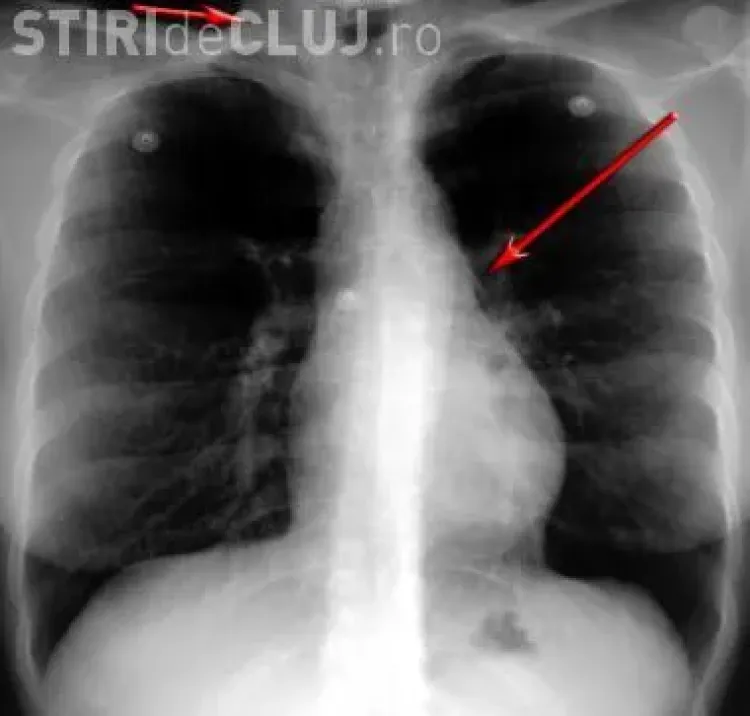

Băiețelul a fost adus din Baia Mare și a fost resuscitat fiind în stare foarte gravă. Cornel Aldea, managerul Spitalului de Copii Cluj, a declarat că băiețelul a înghițit sâmburi de migdale, ”pe care i-a aspirat și i-au ajuns în plămâni”.

Pentru că se sufoca, medicii au fost nevoiți să îi facă o intervenție deosebit de riscantă, i-au aspirat plămânii. Astfel au fost scoși câțiva sâmburi de migdale, pe care copilul i-a introdus în gură și i-a înghițit.